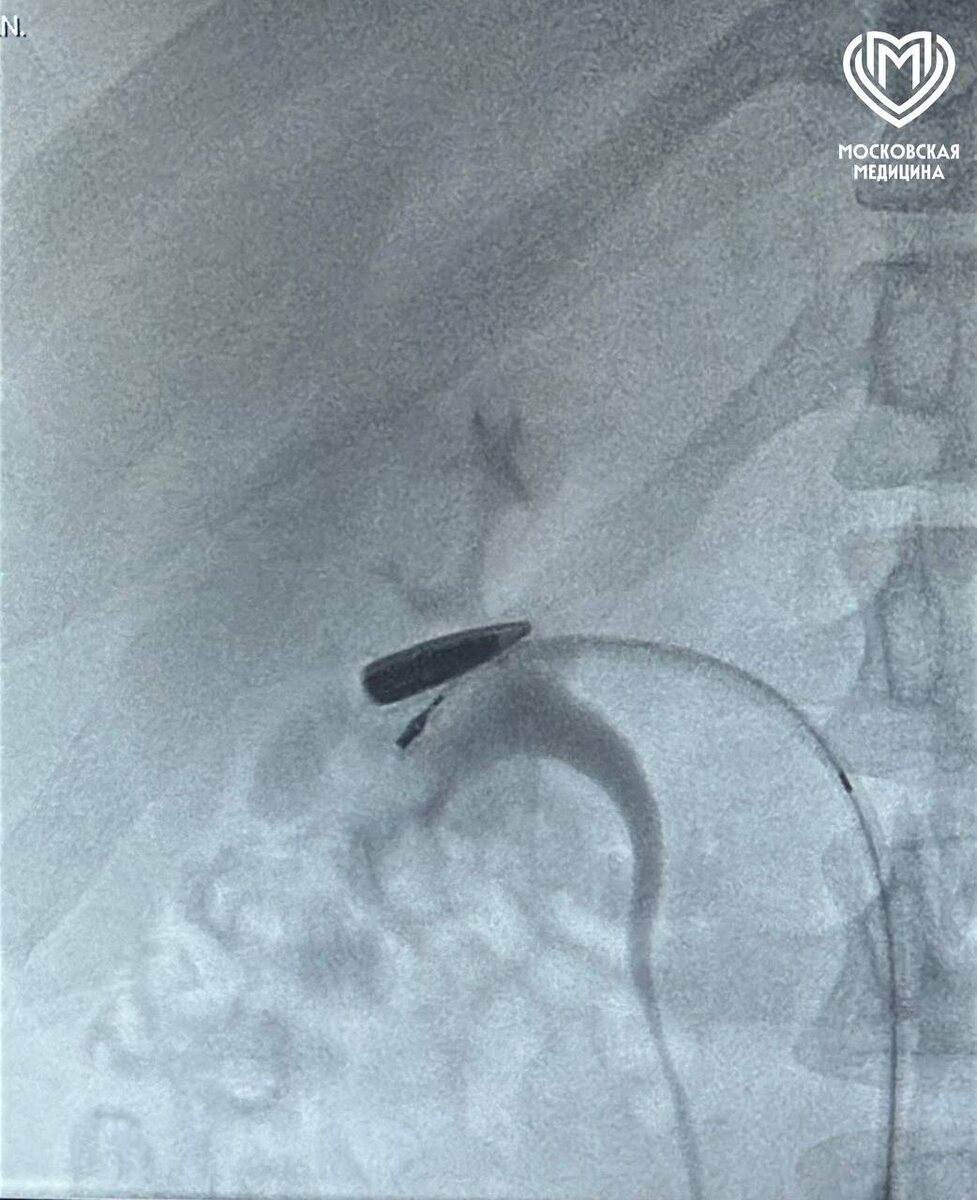

Автоматная пуля проплыла по венам от ключицы до почки у раненого из Курской области.

Пациента доставили вертолетом в институт Склифосовского. Московские врачи на КТ заметили, что пуля калибра 5,45 мм прошла через верхнюю и нижнюю полые вены и остановилась в правой почечной — это редчайший случай.

Хирурги пережали поражённые сосуды, извлекли пулю за семь минут и восстановили кровоток. Почка не пострадала.